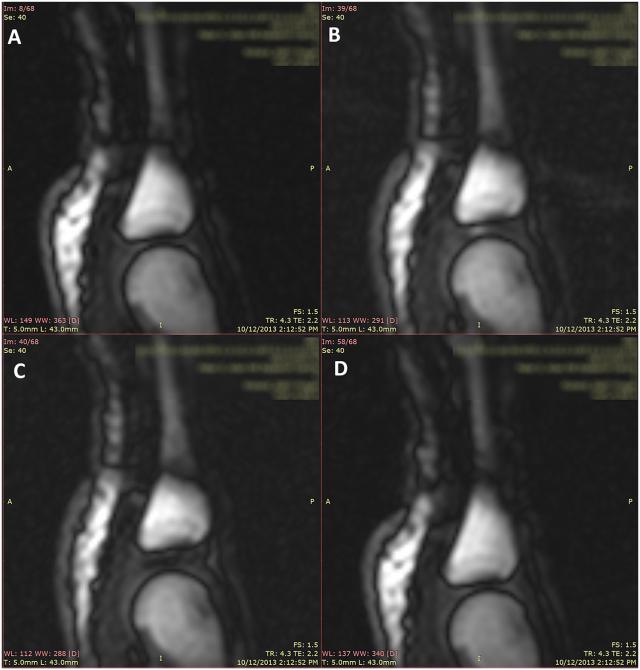

自然,也有一些不同的观点。2005 2008年,加拿大科研团队动态磁共振扫描手指关节。他们发现手指关节之间充满了滑液。当手指被拉动时,滑液也会发生相应的变化。在这个过程中,滑液中会出现气体,并在滑液中产生气泡。这个气泡一直存在,直到手指发出“咔嚓”的声音。所以,他们认为掰手指时的声音并不是由气泡破裂引起的,而是与关节内腔形成有关。